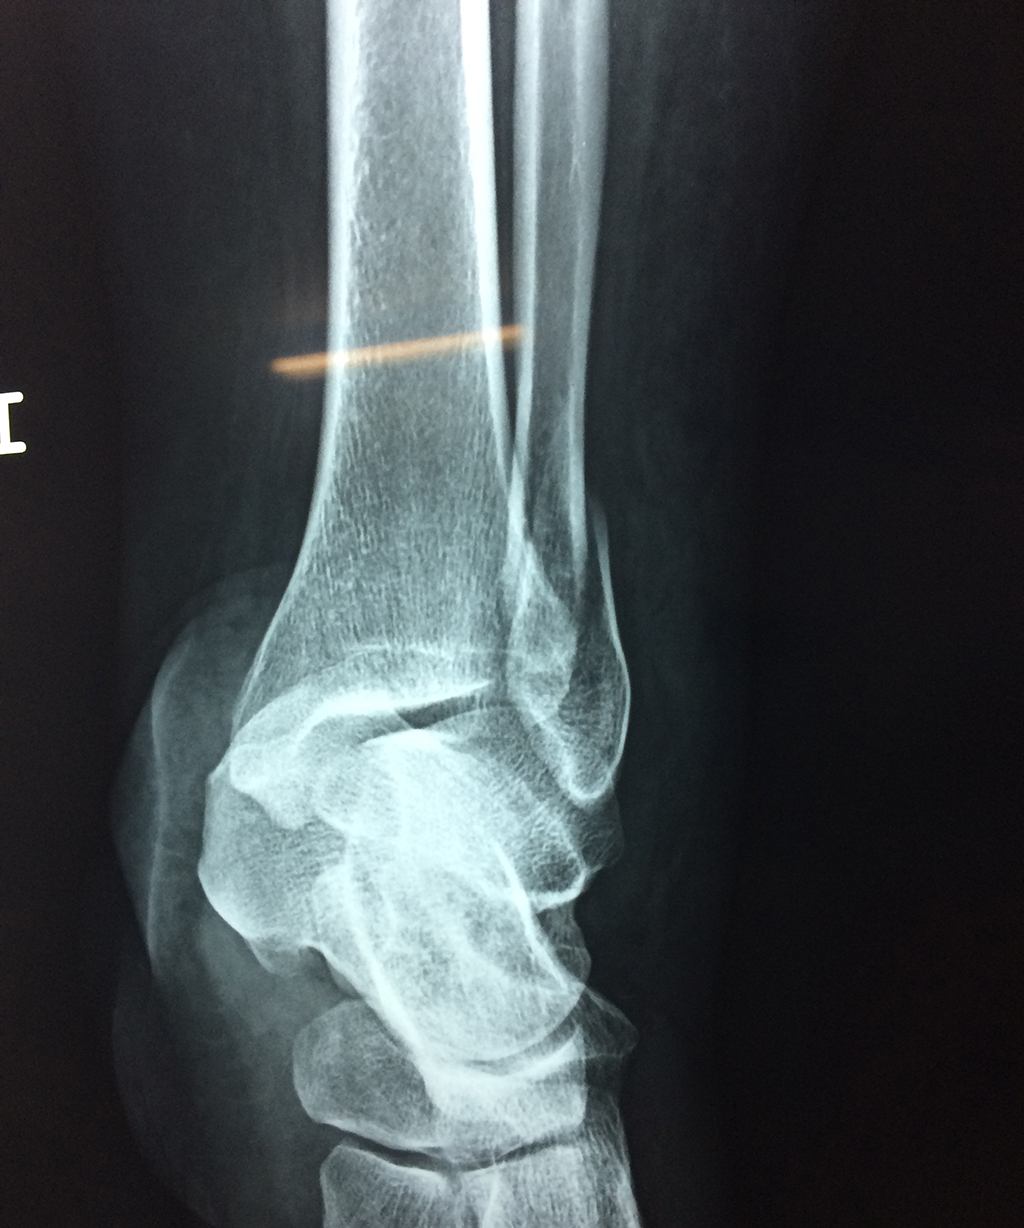

Una fractura de tobillo es la rotura de uno o más de los huesos del tobillo. Estas fracturas pueden ser:

Algunas fracturas de tobillo pueden requerir cirugía si:

- Los extremos de los huesos están desalineados entre sí (desplazados).

- La fractura se extiende hasta la articulación del tobillo (fractura intra-articular).

- Los tendones o ligamentos (tejidos que sujetan los músculos y los huesos entre sí) están rotos.

- El médico cree que sus huesos probablemente no sanen apropiadamente sin cirugía.

- El médico considera que la cirugía puede permitirle una recuperación más rápida y confiable.

- En los niños, la fractura involucra la parte del hueso del tobillo donde el hueso está creciendo.

Cuando se necesita cirugía, es probable que esta implique el uso de clavijas de metal, tornillos o placas para sostener los huesos en su lugar mientras la fractura se consolida. Los elementos de soporte pueden ser temporales o permanentes.